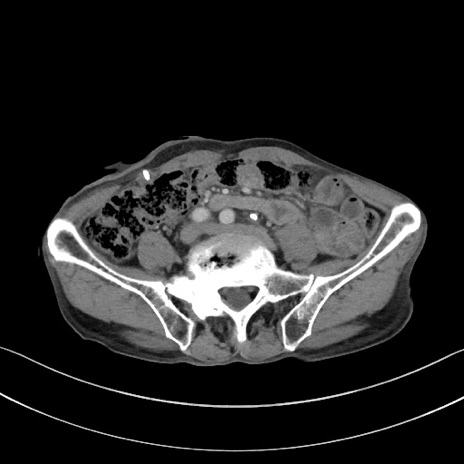

矢状断像

【症例】 70歳代男性

【主訴】右鼠径部腫瘤、疼痛

【現病歴】本日朝より上記主訴あり、受診。

【既往歴】膀胱癌にて膀胱全摘、両側尿管皮膚瘻

【データ】WBC 5600、CRP 0.56